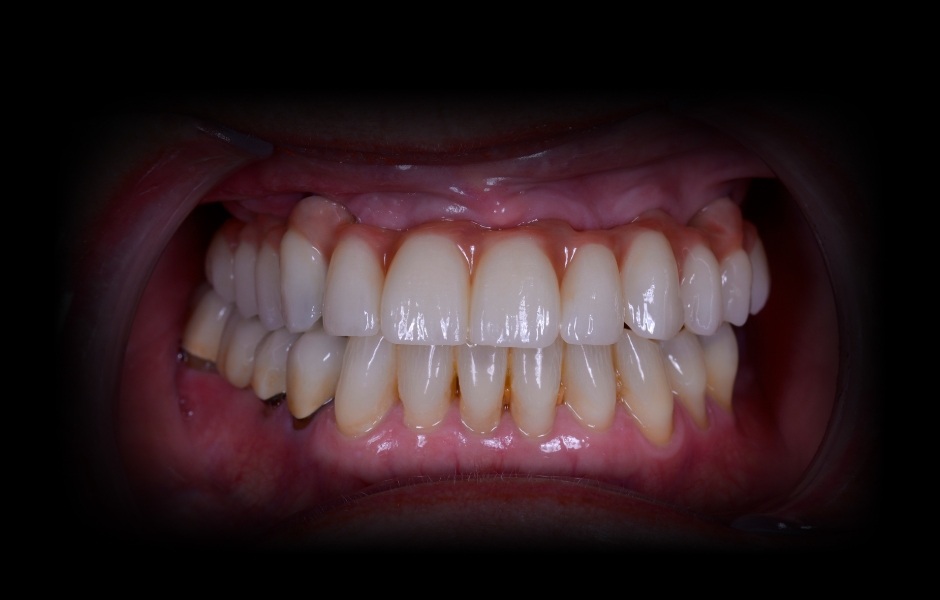

Obr. 28: Nasazená definitivní rekonstrukce.

Obr. 29: Harmonicky sladěné zubní oblouky.